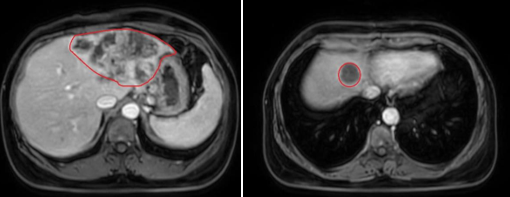

- Chụp cộng hưởng ổ bụng: Nhu mô gan hạ phân thùy II, III, IV, VIII có vài khối, kích thước lớn nhất 120x67 mm, bờ không đều ranh giới không rõ, co kéo bờ gan lân cận, tăng tín hiệu trên T2W hạn chế khuếch tán trên DWI/ADC, sau tiêm ngấm thuốc không đồng nhất thì động mạch. Vùng rốn gan đầu tụy có vài hạch, hạch lớn nhất kích thước 26x13mm.

Hình 1. Hình chụp MRI: Hình ảnh Nhu mô hạ phân thùy hạ phân thùy II, IV, VIII có vài khối .Nhu mô gan hạ phân thùy II, III, IV, VIII có vài khối, kích thước lớn nhất 120x67 mm, bờ không đều ranh giới không rõ, co kéo bờ gan lân cận(viền màu đỏ)

Hình ảnh chụp cắt lớp vi tính sau 3 chu kỳ điều trị hóa chất: gan biến đổi hình thái, bờ không đều, phì đại hạ phân thùy 1. Nhu mô đồng nhất trước và sau tiêm thuốc cản quang. Vị trí hạ phân thùy 2,3,4,8 có các khối tổn thương kích thước lớn nhất 97x67mm, trước tiêm giảm tỷ trọng, sau tiêm ngấm thuốc kém, nhấm viền ngoại vi, xâm lấn gây huyết khối nhánh trái tĩnh mạch cửa.

Hình 2. Vị trí hạ phân thùy 2,3,4,8 có các khối tổn thương kích thước lớn nhất 97x67mm, trước tiêm giảm tỷ trọng, sau tiêm ngấm thuốc kém, nhấm viền ngoại vi( viền màu đỏ)

NHẬN XÉT: Sau 3 đợt điều trị, kích thước khối u giảm một phần (khối lớn nhất có kích thước 120x67mm giảm xuống còn 97x67mm) cho thấy có đáp ứng sau điều trị, chỉ số CA19-9 được duy trì ổn định trong giới hạn bình thường cho thấy không có dấu hiệu tăng sinh tiến triển của khối u, chức năng gan được bảo tổn sau 3 đợt điều trị. Điều này cho thấy phương pháp điều trị đang giúp kiểm soát tình trạng bệnh một cách hiệu quả, mang lại hy vọng tích cực cho quá trình điều trị tiếp theo.